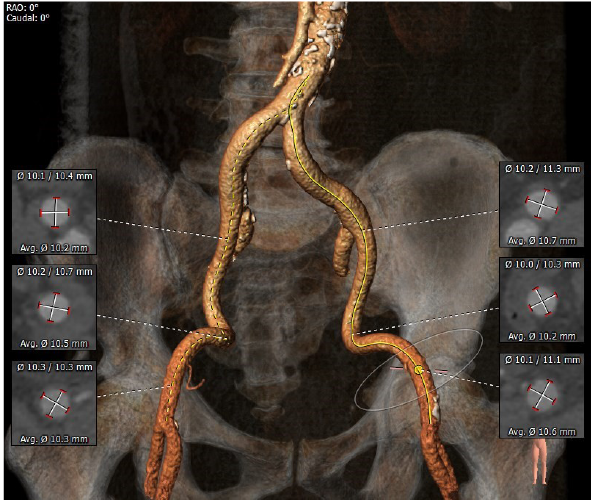

瓣环直径26.7

左室流出道直径:30.8

升主动脉增宽

冠脉高度尚可。左冠高度:13.4,右冠高度:20.6。心脏角度52

入路粗稍弯曲

1. 瓣膜型号及球囊:瓣环26.7mm,左室流出道30.8mm,考虑32VenusA Plus瓣膜,

4. 入路情况:入路直径较粗,稍弯曲,右股作为主入路

5.其他风险:心脏角度偏横位心,升主增宽,增加过弓难度,置入输送器时可调整超硬导丝调整方向延小弯侧方向靠。心尖较薄注意超硬导丝塑形防止心尖穿孔。